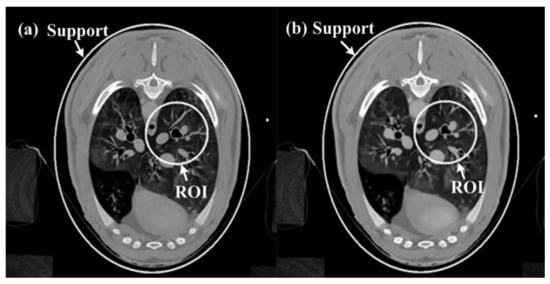

According to the equal-angle fan-beam HLCC, the DCs of a normal dose and low dose were calculated as 2.9965 × 103 and 3.1623 × 103, respectively, and the parameters of the SIRDL + HL algorithm were set, as shown in Table 2. The reconstruction results of the five different algorithms for normal dose are shown in Figure 6. The representative profiles along the horizontal and vertical lines are shown in Figure 7. The above experiments were repeated with a low-dose sinogram, and corresponding results are shown in Figure 8 and Figure 9. The experimental results show that the image support constraint has a strong influence on the TV-based interior reconstruction method, and the reconstruction results of the SIRDL + HL algorithm basically eliminate the DC offset artifacts. The reconstructed image quality based on the TV constraint decreased significantly when the number of view angles was 580, while the reconstructed image quality of the SIRDL + HL method was basically the same as that of the full-view data. The reconstructed image quality based on the TV constraint had serious block artifacts when the number of view angles was 290, while the reconstructed image quality of this algorithm could obtain high reconstruction image quality.

Figure 8.

Reconstructed ROIs from low-dose real sheep projection data using five different methods:(a) SIRTV + BOS; (b) SIRTV + OS; (c) SIRDL + BOS; (d) SIRDL + OS; (e) SIRDL + HL. The display window is [−700 800]HU.